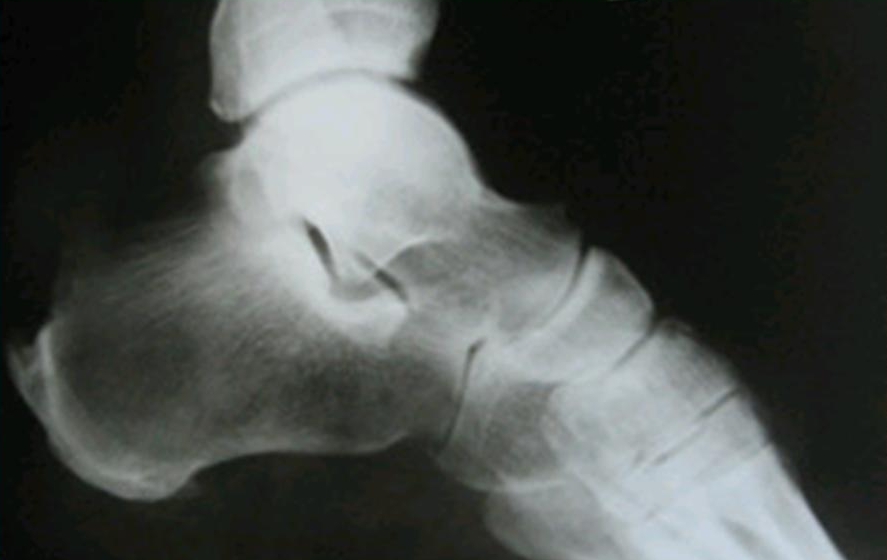

Диагностика

Рентгенография предоставляет полную информацию о состоянии пациента. Снимок выполняется в боковой проекции, и на основании полученных данных врач может определить прогрессирование болезни Хаглунда-Шинца. Это основано на уплотнении бугра, увеличенной щели между ним и пяточной костью, а также на неравномерной, пятнистой структуре ядра окостенения (см. фото).

На поздних стадиях заболевания на рентгеновском снимке четко видна губчатая структура новой костной ткани. В сложных случаях для более точной диагностики полезно сравнить рентгенограммы больной и здоровой стопы. Важно провести дифференциальную диагностику, чтобы исключить: